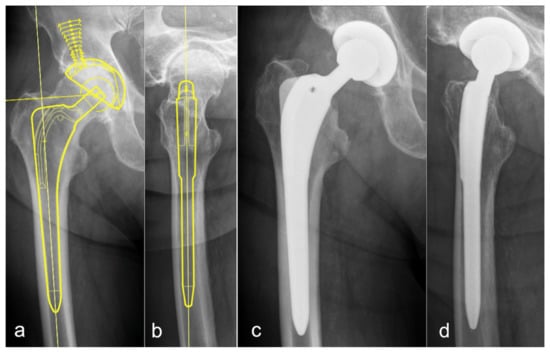

3.1. Conventional Stem Total Hip Arthroplasty (CTHA)—Conventional Templating in One Plane on the a.p. Pelvic Overview

3.2. CTHA—Templating in Two Planes—a.p. and Lateral View